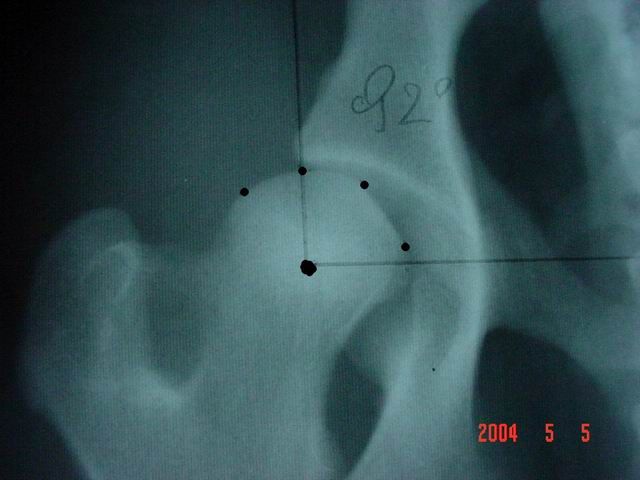

Kattintás=nagyításEnyhe fokú a dysplasia, ha az ízületi rés kissé kiszélesedett divergáló, a vápa laposabb, a combcsontfej nem teljesen szabályos kör alakú, a szög 100° körüli. Enyhe gyulladásra utaló tünetek előfordulhatnak (Morgan-vonal, scleroticus gyűrű, elülső vápakontúron felrakódás).